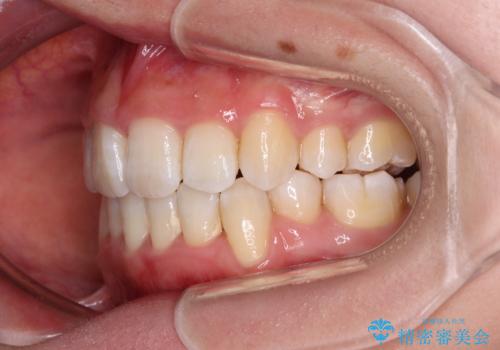

- 上下前歯の八重歯やデコボコと、唇の閉じにくさを気にして来院された患者様です。

口元の突出感を改善するため、上下左右の第一小臼歯4本を抜歯し、ワイヤー装置にて矯正治療を行うこととしました。

デコボコの解消で歯が磨きやすくなり、抜歯矯正により口元の突出感が大幅に改善され、スッキリした口元になりました。